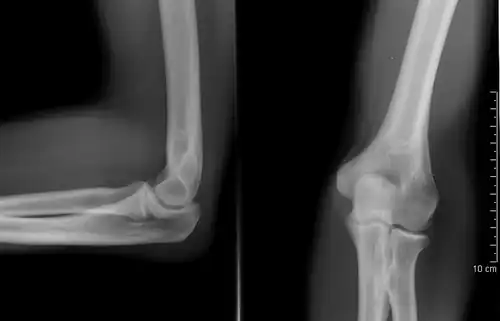

Development

The elbow undergoes dynamic development of ossification centers through infancy and adolescence, with the order of both the appearance and fusion of the apophyseal growth centers being crucial in assessment of the pediatric elbow on radiograph, in order to distinguish a traumatic fracture or apophyseal separation from normal development. The order of appearance can be understood by the mnemonic CRITOE, referring to the capitellum, radial head, internal epicondyle, trochlea, olecranon, and external epicondyle at ages 1, 3, 5, 7, 9 and 11 years. These apophyseal centers then fuse during adolescence, with the internal epicondyle and olecranon fusing last. The ages of fusion are more variable than ossification, but normally occur at 13, 15, 17, 13, 16 and 13 years, respectively.[16] In addition, the presence of a joint effusion can be inferenced by the presence of the fat pad sign, a structure that is normally physiologically present, but pathologic when elevated by fluid, and always pathologic when posterior.[17]